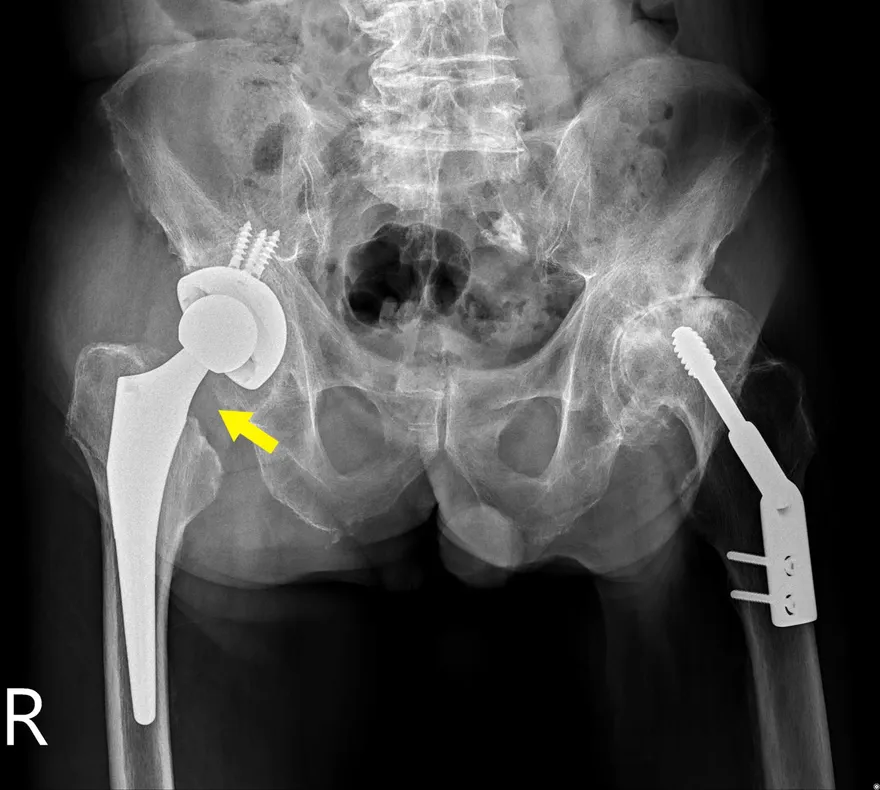

跌倒

髖部

人工髖關節置換手術

股骨頸骨折

骨盆X光